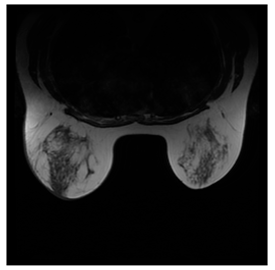

Breast-MRI-NACT-Pilot is an MRI-type image database, collecting breast medical images of 64 patients. Some samples are shown in Figure 12a.

Figure 12.

Sampled images in the tested benchmark databases: (a) Breast-MRI-NACT-Pilot (breast), (b) ACRIN-DSC-MR-Brain (brain), (c) NIH (chest), (d) Lung-PET-CT-Dx (lung), (e) Prostate-MRI (prostate), and (f) Other grayscale standard images.

- Prostate-MRI Database (available at: https://wiki.cancerimagingarchive.net/display/Public/PROSTATE-MRI (accessed on 4 November 2021))

Prostate-MRI database contains MRI-type medical images and collects prostate medical images. Some samples are shown in Figure 12e.